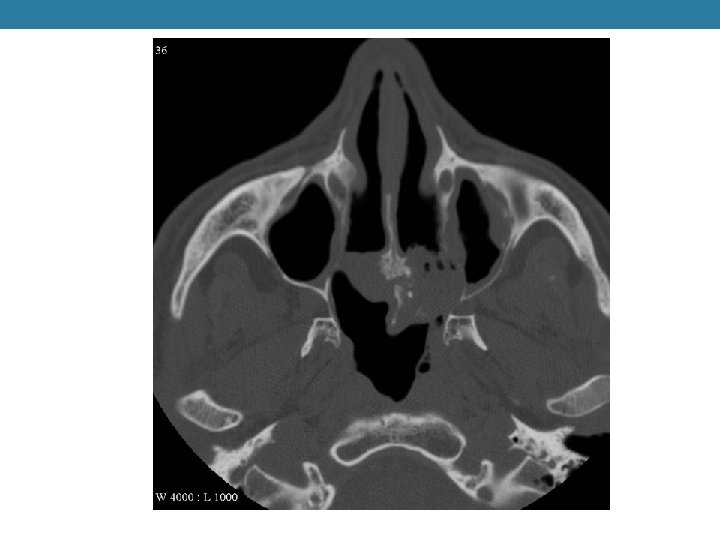

Diagnostico

TAC